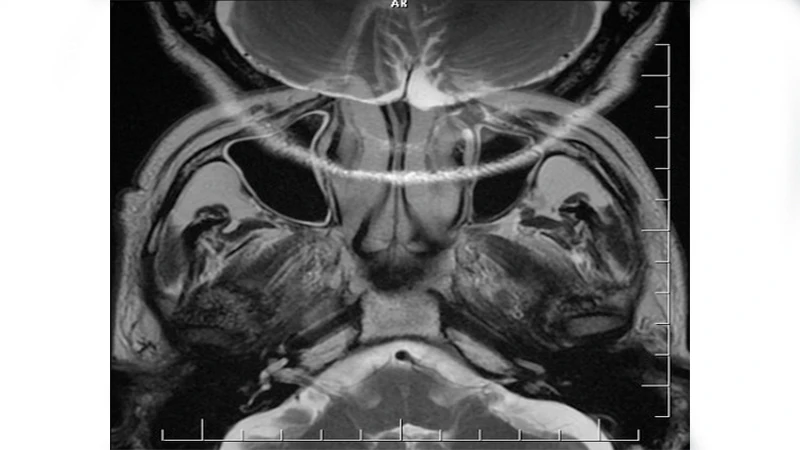

3. Aliasing or "Wrap-Around" Artifact (MRI)

This is a specific MRI artifact that occurs when the Field of View (FOV) is set too small for the body part being scanned. Anatomy that is outside the FOV gets "wrapped around" and appears on the opposite side of the image.

- Appearance: A portion of the anatomy (e.g., the nose in a brain scan, or an arm in an abdomen scan) appears superimposed on the other side of the image.

- Cause: The scanner misinterprets the spatial location of signals coming from outside the prescribed FOV.